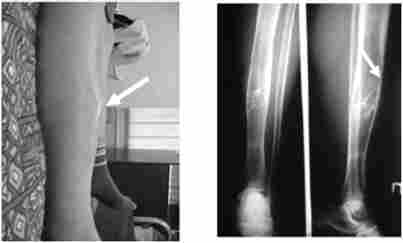

Характерна деформація правої великогомілкової кістки (поднадкостнічная кіста) у хворої, що страждала первинним гіперпаратиреоз

Мал. 7.1. Характерна деформація правої великогомілкової кістки (поднадкостнічная кіста) у хворий, що страждала первинним гіперпаратиреоз